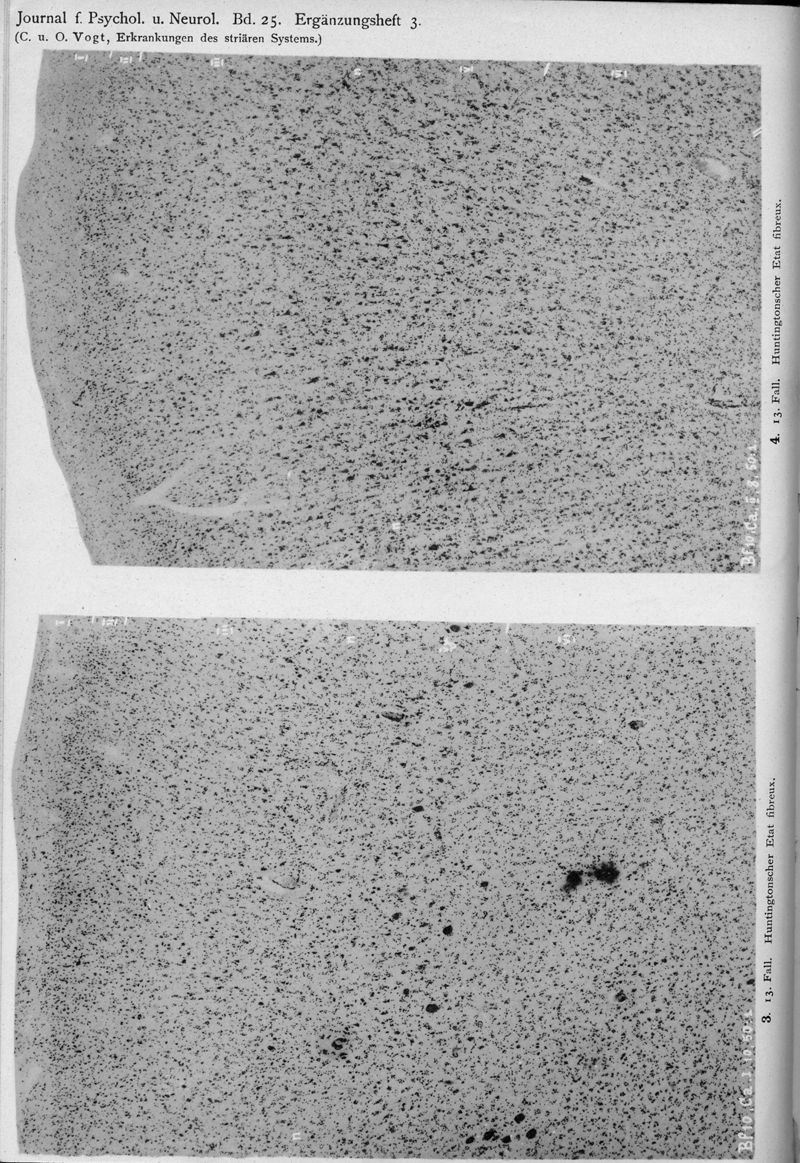

VOGT, Cécile / VOGT, O.

In : Journal für Psychologie und Neurologie,

1920, Vol. 25, pp. 627-846